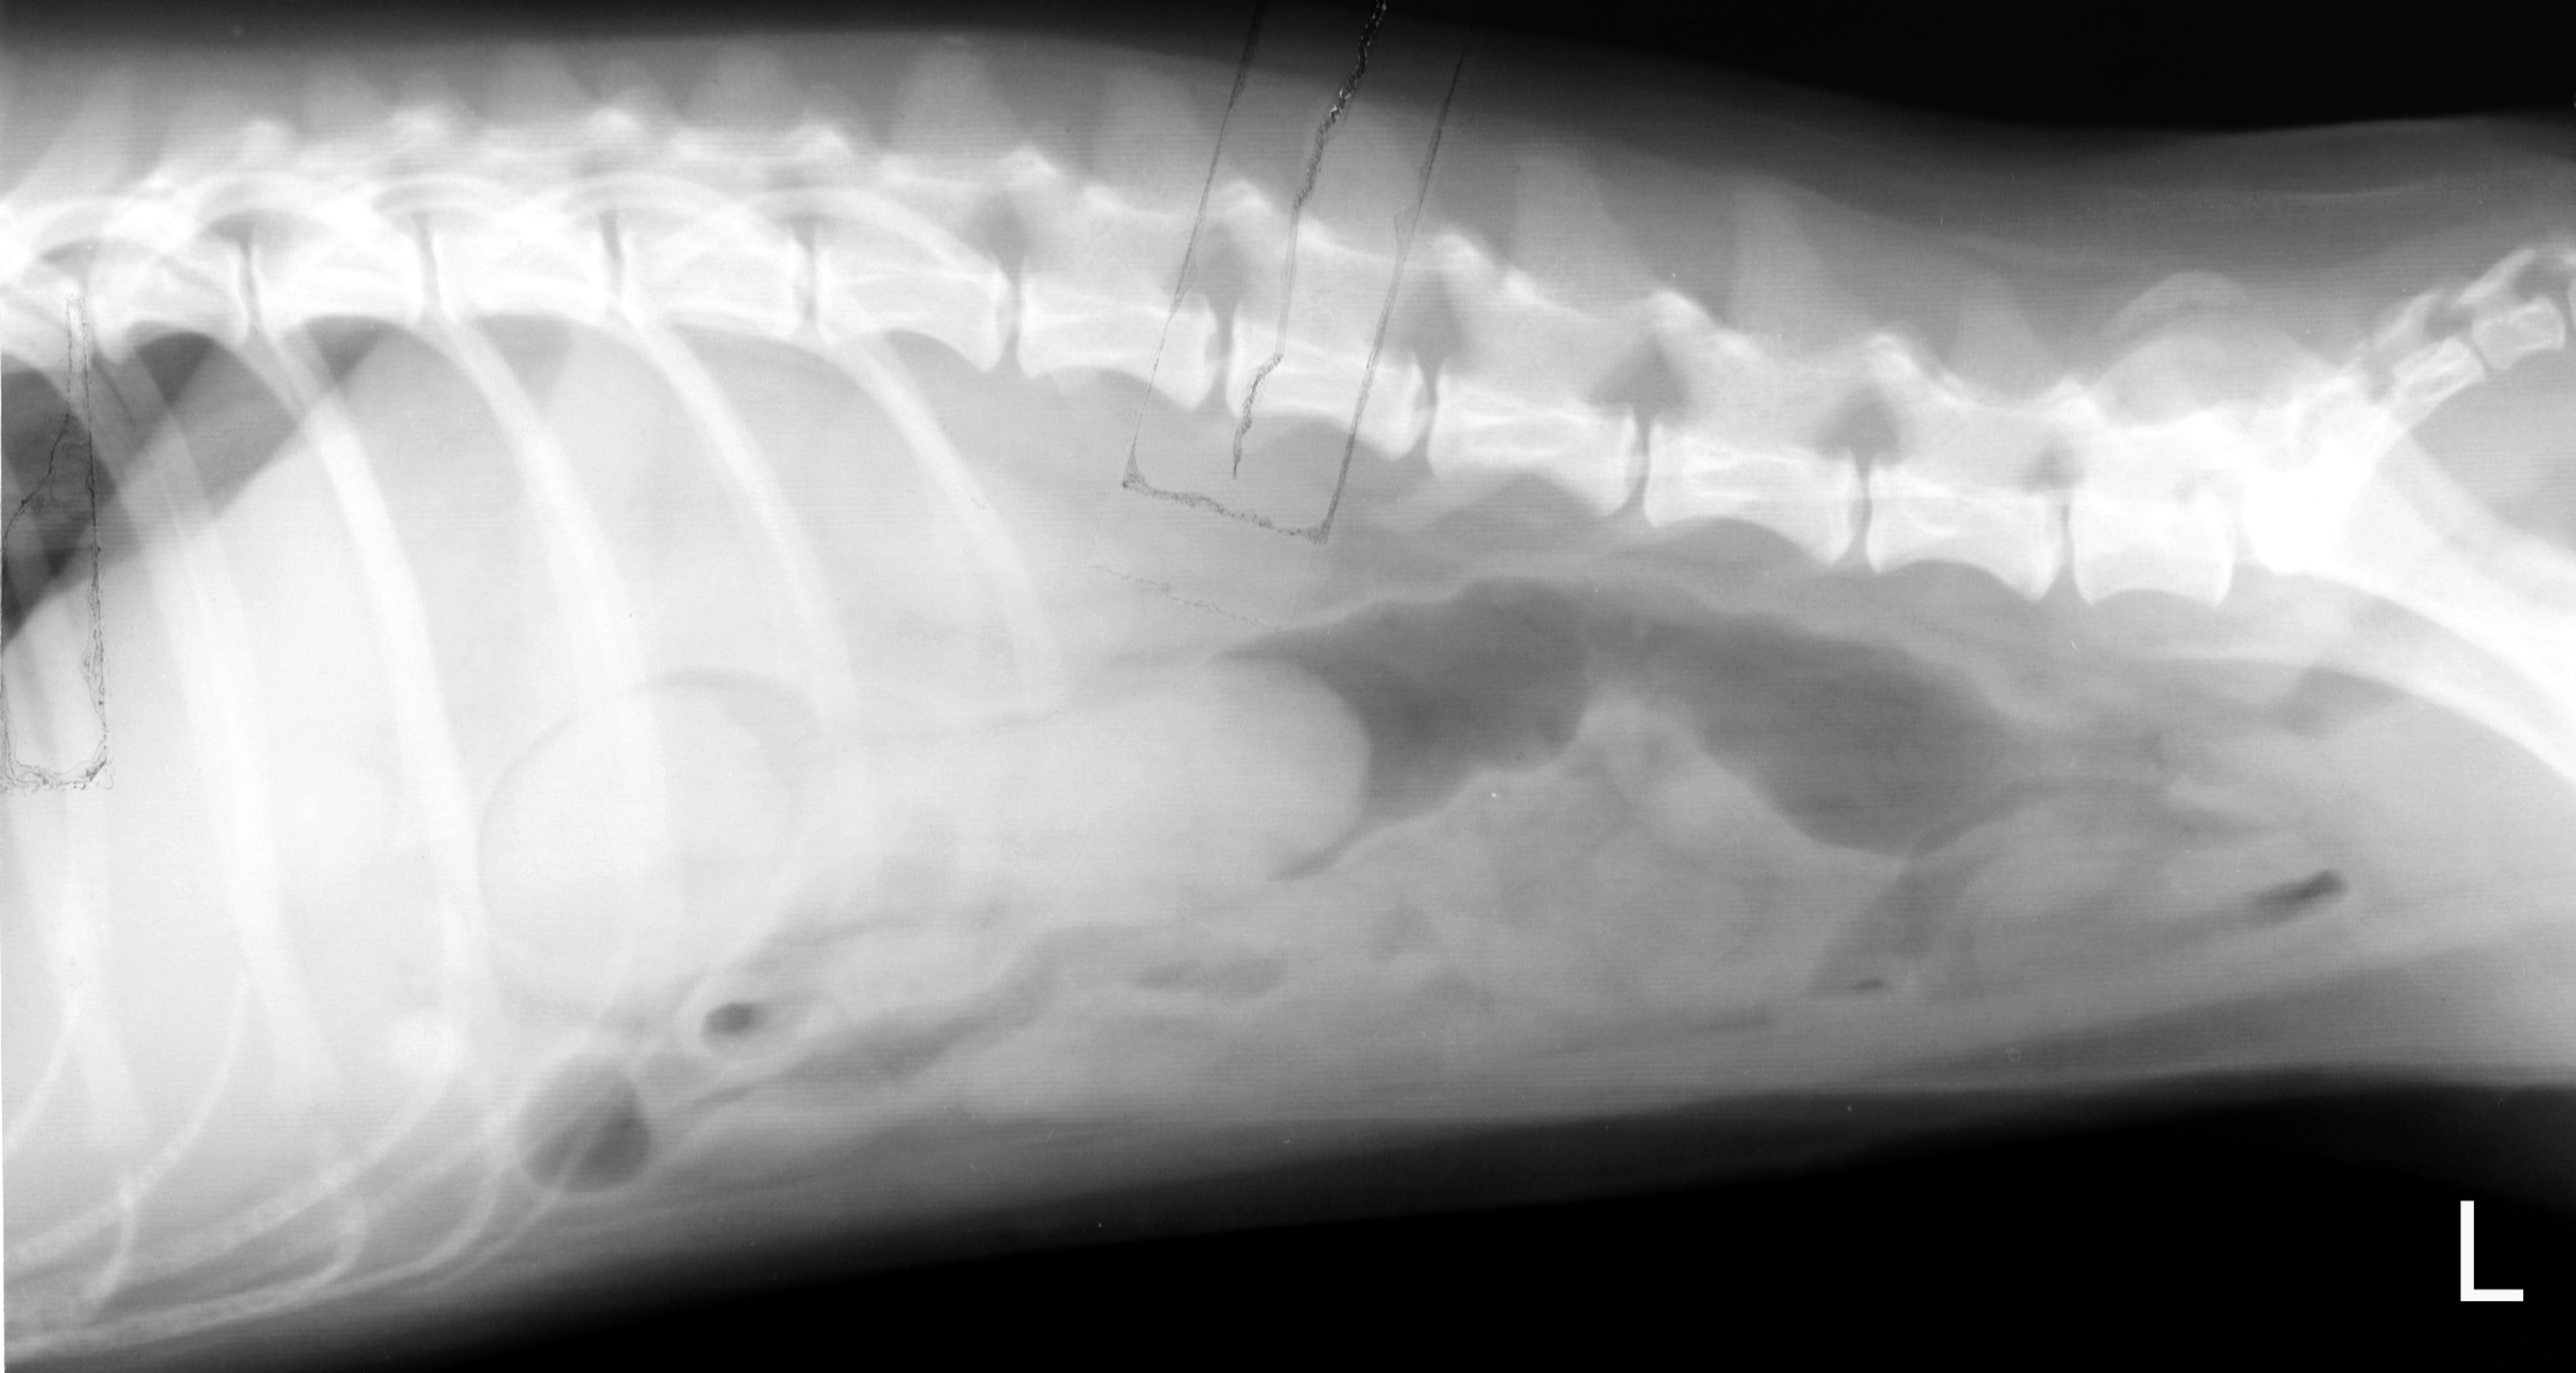

Ileocecolic intussusception, dog, lateral view

Lateral radiograph of a 10-month-old mixed-breed dog with an ileocecocolic intussusception.